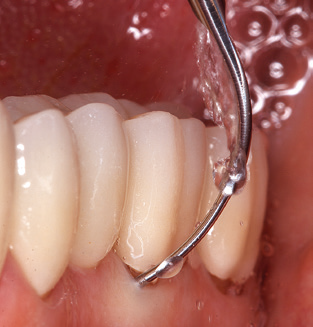

The current working concept for SPT

Fig. 4: Flexible probes with millimetre markings are recommended for the probing of dental implants (e.g. Colorvue Kit PCV11KIT6, Hu­Friedy). – Fig. 5a and b: A straight working tip (1P, W&H Dentalwerk Bürmoos GmbH) is a suitable instrument for use on all natural teeth. – Fig. 6: Curved working tips (3Pr/3Pl, W&H Dentalwerk Bürmoos GmbH) lend themselves to the processing of difficult-to-reach areas of the tooth and root surfaces (e.g. furcations). – Fig. 7: The tapered, hexagonal implant cleaning tip (1I, W&H Dentalwerk Bürmoos GmbH) permits atraumatic and efficient cleaning of the crown and abutment surfaces. – Fig. 8: Titanium and carbon curettes are suitable instruments for the manual cleaning of the implant surfaces.

Updating the patient’s medical history is an important aspect of SPT and should occur at least once per year. It helps the dental team to identify and document any new risk factors. Especially when a patient is treated over many years, it is important to establish whether patient-specific and general health risk factors have changed. This primarily concerns a heightened risk as a result of diabetes, but other general conditions (cardiovascular disease and neoplasia) can also produce a modified risk profile as a result of the treatment performed and medication administered. Accordingly, updating the medical history as part of SPT is very important, as a modified risk profile may trigger the need to adapt the treatment interval. In the next step, it is important to afford the diagnostics due attention. Whilst instruments are a central aspect of SPT, findings and their documentation must never be neglected. The periodontological findings are essential for a good diagnosis; increases in the pocket depths and the BOP index are clear indicators of advancing periodontal and peri-implant disease. As such, the team should not shy away from probing implants too, with the aim of gathering the requisite data. At the same time, it is important to use periodontal probes with millimetre markings. Metallic probes have already been used for determining pocket depths around natural teeth for decades. In the case of implants, the challenge of recording correct and reproducible pockets depths is even greater. As the discrepancy between the implant diameter and the contour of the superstructure regularly results in overcontouring of the superstructure, flexible probes which still feature millimetre markings are a sensible solution for measuring pocket depths around implants (e.g., Colorvue Kit PCV11KIT6, Hu­Friedy; Fig. 4).